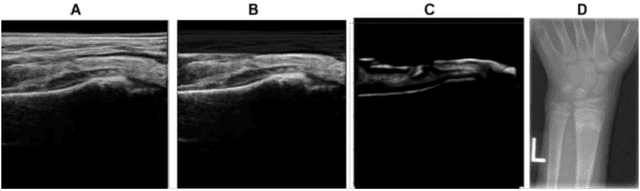

Abstract:Most applications of deep learning techniques in medical imaging are supervised and require a large number of labeled data which is expensive and requires many hours of careful annotation by experts. In this paper, we propose an unsupervised, physics driven domain specific transporter framework with an attention mechanism to identify relevant key points with applications in ultrasound imaging. The proposed framework identifies key points that provide a concise geometric representation highlighting regions with high structural variation in ultrasound videos. We incorporate physics driven domain specific information as a feature probability map and use the radon transform to highlight features in specific orientations. The proposed framework has been trained on130 Lung ultrasound (LUS) videos and 113 Wrist ultrasound (WUS) videos and validated on 100 Lung ultrasound (LUS) videos and 58 Wrist ultrasound (WUS) videos acquired from multiple centers across the globe. Images from both datasets were independently assessed by experts to identify clinically relevant features such as A-lines, B-lines and pleura from LUS and radial metaphysis, radial epiphysis and carpal bones from WUS videos. The key points detected from both datasets showed high sensitivity (LUS = 99\% , WUS = 74\%) in detecting the image landmarks identified by experts. Also, on employing for classification of the given lung image into normal and abnormal classes, the proposed approach, even with no prior training, achieved an average accuracy of 97\% and an average F1-score of 95\% respectively on the task of co-classification with 3 fold cross-validation. With the purely unsupervised nature of the proposed approach, we expect the key point detection approach to increase the applicability of ultrasound in various examination performed in emergency and point of care.

Abstract:Ultrasound examination for detecting fractures is ideally suited for Emergency Departments (ED) as it is relatively fast, safe (from ionizing radiation), has dynamic imaging capability and is easily portable. High interobserver variability in manual assessment of ultrasound scans has piqued research interest in automatic assessment techniques using Deep Learning (DL). Most DL techniques are supervised and are trained on large numbers of labeled data which is expensive and requires many hours of careful annotation by experts. In this paper, we propose an unsupervised, domain specific transporter framework to identify relevant keypoints from wrist ultrasound scans. Our framework provides a concise geometric representation highlighting regions with high structural variation in a 3D ultrasound (3DUS) sequence. We also incorporate domain specific information represented by instantaneous local phase (LP) which detects bone features from 3DUS. We validate the technique on 3DUS videos obtained from 30 subjects. Each ultrasound scan was independently assessed by three readers to identify fractures along with the corresponding x-ray. Saliency of keypoints detected in the image\ are compared against manual assessment based on distance from relevant features.The transporter neural network was able to accurately detect 180 out of 250 bone regions sampled from wrist ultrasound videos. We expect this technique to increase the applicability of ultrasound in fracture detection.